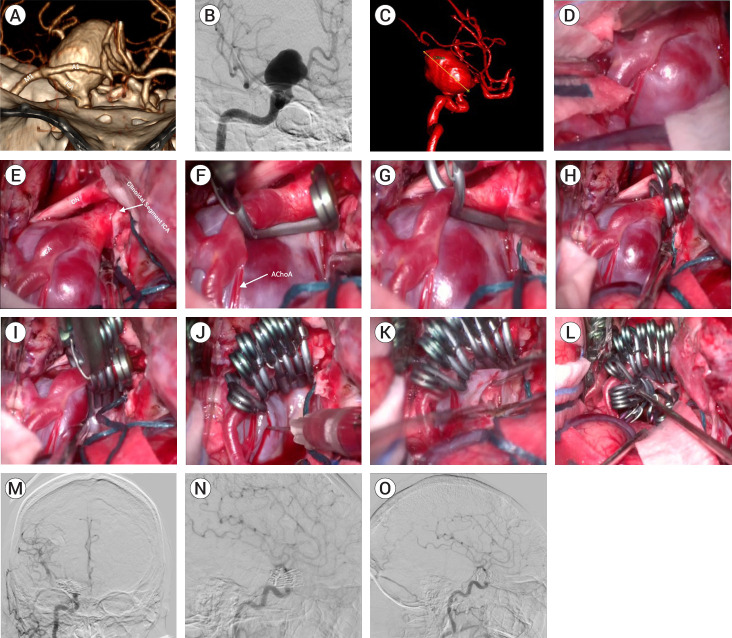

复杂动脉瘤是当代神经外科的治疗难题。目前已提出了几种显微外科和血管内治疗技术。栅栏式剪切技术使用栅栏式夹子,这种夹子的堆叠不是为了重建动脉瘤的颈部,而是通过重建穹顶来创建一个管道,使脑流正常化。我们介绍了四例使用篱笆夹技术的病例。这些动脉瘤的位置不同(ICA、MCA、AComA),体积较大或巨大,颈部较宽,无法使用传统技术进行剪切,因此必须使用非常规剪切技术,并取得了良好的效果。在我们的经验中,我们发现这种技术对大型和巨型宽颈动脉瘤非常有用,它可以根据理想闭合线的概念在这些以前未报道过的位置重建母血管,从而恢复正常的脑循环。使用非常规技术剪切复杂动脉瘤可以单独使用,也可以联合使用以进行充分治疗,在保留脑循环的同时不影响动脉瘤的充分切除。栅栏技术是一种可行的剪切技术,对于颈部较宽的巨大动脉瘤来说,它是一种发病率较低的选择。

Complex aneurysms are a therapeutic challenge in contemporary neurosurgery. Several microsurgical and endovascular techniques have been proposed for their treatment. The picket fence clipping technique uses fenestrated clips, that are stacked not to reconstruct the neck of the aneurysm, but to create a duct to normalize the cerebral flow by reconstructing the dome. We present four illustrative cases using the picket fence clipping technique. The aneurysms considered were of different locations (ICA, MCA, AComA), of large or giant size with wide necks, in which clipping attempt with a conventional technique was not possible, so that the use of non-conventional clipping techniques had to be applied with favorable results. In our experience we found this technique useful in large and giant, wide-necked aneurysms by reconstructing the parent vessel according to the concept of the ideal closure line in these previously unreported locations, thereby restoring normal cerebral circulation. The use of non-conventional techniques for clipping complex aneurysms can be used alone or in combination for adequate treatment, preserving cerebral circulation without compromising adequate exclusion of the aneurysm. The Picket fence technique is a feasible clipping technique that can be used as a less morbid option in large and giant aneurysms with wide necks.